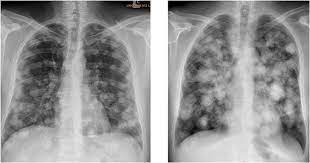

How To Know If Testicular Cancer Has Spread To Lungs / Orchid Results : Lump or swelling in your neck, under your arm, or in your groin.. This is not lung cancer. If testicular cancer has spread to other parts of your body, you may also experience other symptoms. When testicular cancer spreads, it most commonly spreads to the lung and the lymph nodes of the chest, pelvis, and the base of the neck. It's not called lung cancer unless it starts from cells in the lung. Good prognosis means that your primary cancer was in your testicle, or at the back of your stomach or abdomen (retroperitoneal).

The best way to confirm the diagnosis of testicular cancer is to remove the testicle. As others have said this is a type of cancer which does not behave in the same way as most. Swelling and enlargement of male breasts. For example, breast cancer that spreads to the lung is called metastatic breast cancer, not lung cancer. These cancers have spread to a distant lymph node or the lungs. As with other forms of cancer, testicular cancer can spread, or metastasize, to other areas of the body. In stage 3 of the disease, the cancer has invaded other organs such as the lungs, brain or liver. This is testicular cancer which has spread to the lungs. If testicular cancer spreads, it can spread to the following: Which treatment your doctor will choose to treat it is based on the type of cancer you have and if it has spread. Cancer is always named for the place where it starts. So when testicular cancer spreads to the lung (or any other place), it's still called testicular cancer. Liver is pretty close to the lungs.

Headaches or confusion, from cancer spread in the brain. But most of the time they're on the edges of your lungs or in the lower lobes. Swelling of 1 or both legs or shortness of breath from a blood clot can be symptoms of testicular cancer. The tumour has only spread to the abdominal lymph nodes or the lungs or both. Shortness of breath, chest pain, or a cough (even coughing up blood) may develop from cancer spread in the lungs.

Prognostic Factors Of Metastatic Testicular Non Seminomatous Germ Cell Tumors After Chemotherapy Sciencedirect from ars.els-cdn.com This is not lung cancer. Lymph nodes are glands that make up your immune system. Swelling and enlargement of male breasts. The nature (cell type) of the metastatic. Shortness of breath, chronic cough or chest pain can turn out to be the symptoms of testicular cancer that have affected the lungs. As with other forms of cancer, testicular cancer can spread, or metastasize, to other areas of the body. Good prognosis means that your primary cancer was in your testicle, or at the back of your stomach or abdomen (retroperitoneal). If it is not detected and treated, testicular cancer eventually can spread to the lungs, brain, liver, and other parts of the body.

Testicular cancer begins in your testes, the male reproductive organ. Tumor marker protein levels are normal or slightly elevated. Swelling of 1 or both legs or shortness of breath from a blood clot can be symptoms of testicular cancer. Cancer can spread to any part of your lungs. There is no poor prognosis grouping for seminoma testicular cancer. Headaches or confusion, from cancer spread in the brain. Your markers are only slightly above normal (s1 in the tnm staging system). If cancer cells have spread to your lymph nodes (or beyond your lymph nodes to another part of the body), symptoms may include: Stage iii testicular cancer has three subcategories: But most of the time they're on the edges of your lungs or in the lower lobes. A blood clot in a large vein is called deep venous thrombosis or dvt. Testicular cancer is uncommon and, while it can develop at any age, it mainly occurs in men between ages 25 and 44. A lump or swelling in your neck.

Shortness of breath, chest pain, or a cough (even coughing up blood) may develop from cancer spread in the lungs. Symptoms of metastatic testicular cancer can include: Cancer that's spread to other parts of the body is known as metastatic cancer. If testicular cancer has spread to other parts of your body, you may also experience other symptoms. The best way to confirm the diagnosis of testicular cancer is to remove the testicle.